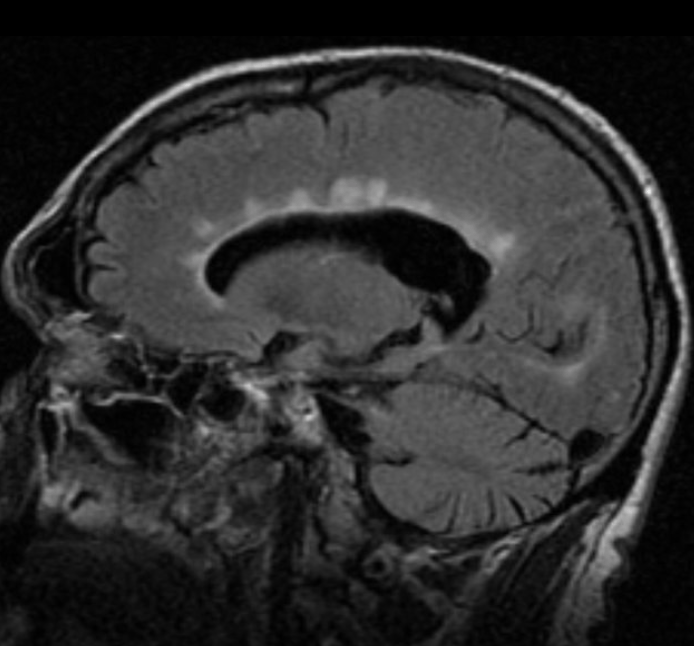

78 y/o F with history of HTN, asthma, and breast cancer s/p resection and radiotherapy presents with AMS, dysarthria, nausea, and vomiting. The following image suggests that the patient may have this pathology.

What is malignancy with metastasis to the brain?